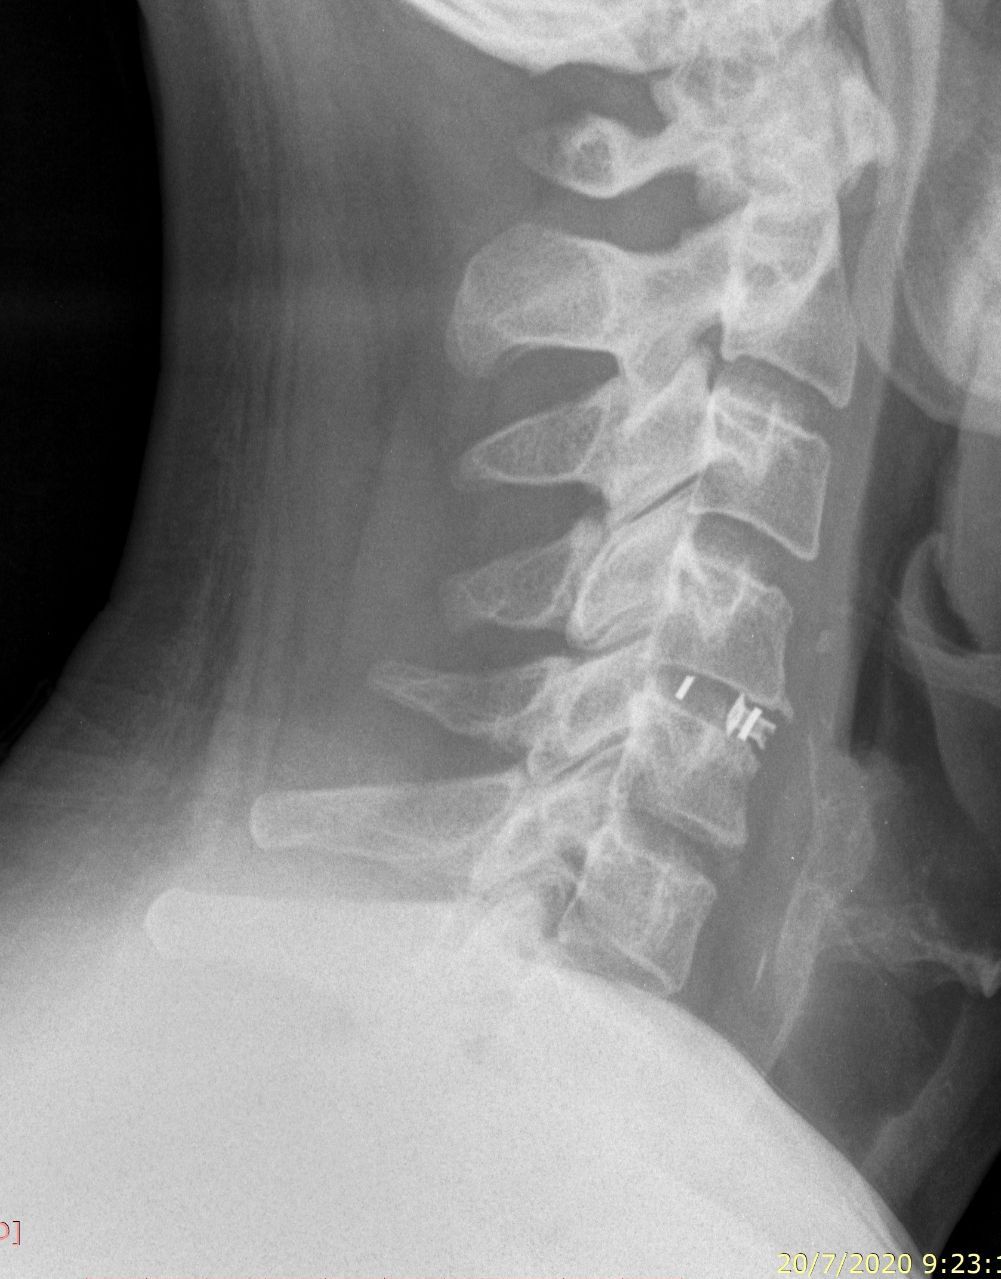

Αυχενική μικροδισκεκτομή και σπονδυλοδεσία A5-6 με cage.